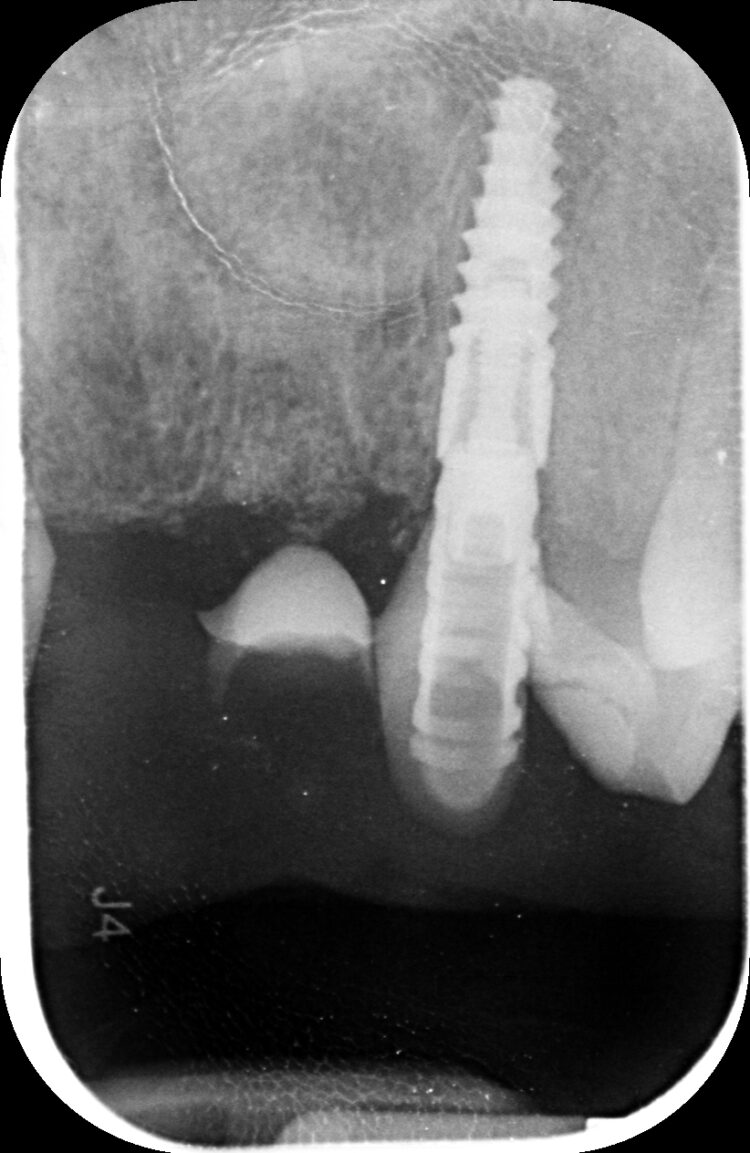

Despite using all the available examination tools, it was still challenging to assess the level of damage to the teeth under the metal ceramic bridge, because the prosthetic material obstructed the x-ray. It was confirmed that two teeth were decayed and fractured, but it was not possible to confidently diagnose the UR2.

The UR2 was assessed and deemed unrestorable. The UR2, UL2 and 3 were then extracted as minimally traumatically as possible.

The two 3.3mm diameter Tapered Pro Conical implants were then placed through the guide at the pre-determined positions, angles and depths. Both implants achieved an insertion torque above 30Ncm.